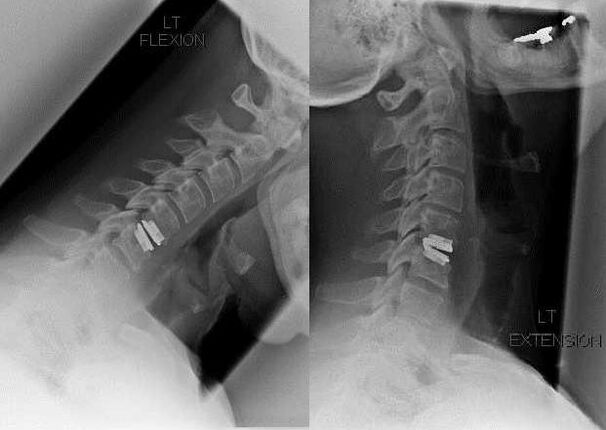

Alamar don shiga tsakani sun hada da rashin ingancin ra'ayin mazan jiya, kazalika da rikitarwa na mahaifa, da cututtukan fata mai ban tsoro, da cututtukan fata mai ban tsoro. Don lalata igiyar fata, tasoshin jini, da kuma tushen spation, ana yin ayyukan da:

A lokacin tiyata, gutsutsuren ƙashin da jijiyoyin ƙasa na iya murƙushe, da kuma fa'idodin Intervertebral na iya zama gaba ɗaya ko kuma a cire shi gaba ɗaya. Don kananan abubuwan da ke cikin hernial, Laser vaporization na Disc na nucleus yawanci ana yin su sau da yawa.

Bayan Bayyanar da tsarin vertebral, yana tabbatar da sassan motsi na spartery shine sau da yawa Fashion Fashion ya buƙaci ko kuma shigarwa na kashi da kuma ciwon ciki.